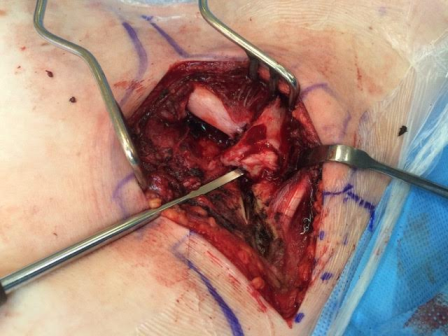

Fig. 4: Intra-operative image showing the rotated medial end of clavicle and disrupted sternoclavicular joint

The patient underwent emergency open reduction through a longitudinal incision along the medial clavicle. Surgical exploration showed the floating fragment, which was rotated and had a partially stripped periosteal sheath (Fig. 4); its medial end had a rough surface, and did not have the appearance of a cartilaginous articular surface, which corresponded to a fracture through the medial physis of the clavicle. Gentle manoeuvres were performed to reduce the fragment. Anatomic reduction and fixation of the lateral fracture with a reconstructive plate (which crossed only the lateral fracture) resulted in reduction of the fracture. Radiographic confirmation of the reduction was obtained and stability was tested with gentle mobilization of the ipsilateral upper extremity and loading of the SC joint. After surgery, the patient was placed in a sling for 4 weeks: progressive resumption of movements and activities was then allowed. After surgery the patient was asymptomatic; examination showed symmetry of the clavicles and of the SC joints, painless and complete range of motion of the left shoulder. Radiographs showed complete consolidation at three months (Fig. 5). The patient has resumed full activities and sports without problems subsequently.

Non-operative treatment and closed reduction are not indicated, as the free fragment cannot be managed. Once excluded a true dislocation of the SC joint, treatment requires open reduction of the two fractures, fixation of the lateral fracture and suture of the torn periosteum at the physeal fracture. No further medial stabilisation is required, as the periosteal tube remains in its anatomic position and the attaching ligaments are intact to the periosteum [14].